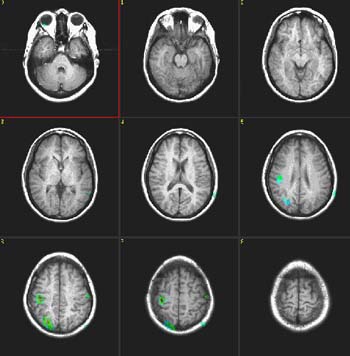

Fluency of Verbs

Right handed, 24 year-old woman |

| Paradigm |

ON: Generate verbs related to nouns (objects)

OFF: Count the letters of presented words |

| Statistics |

| Statistical method |

P Value |

Z score |

| T-Test |

0.0001 |

3.8 |

| Activation |

Broca's area and left SMA are depicted. Some activation appears in the left hippocampal formation and visual areas. This last activation could be explained as the effect of picturing the objects given during the "ON" condition. There is also activation in the right cerebellum and left inferior temporal gyrus.